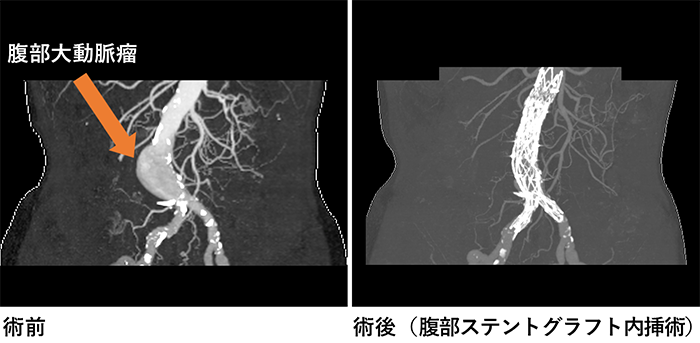

大動脈瘤

大動脈疾患は、特に突然死の原因として心筋梗塞の次に多い疾患とも言われており、その予防と、救急対応が地域にとって重要な問題です。埼玉県東部地域における緊急手術対応可能な医療機関として、一人でも多くの人命を救助できるように、緊急手術にも積極的に対応しております。近隣の地域のみならず、緊急症例においては埼玉県全域および近隣の都道府県からのご依頼にも対応します。

胸部大動脈瘤や腹部大動脈瘤に対する治療としては、人工血管と置換する手術が基本的な根治的治療ですが、形態的な適応と年齢や手術侵襲による影響を考慮して、ステントグラフト挿入術も行っております。 他の心臓血管疾患と同様に大動脈疾患も早期発見と予防が重要です。特に大動脈疾患は、リスクファクターをお持ちの方や、ご家族に大動脈疾患を患ったことのある方には一度検査を受けることをお勧めしています。当科では、動脈硬化の評価とともに、大動脈瘤のスクリーニング検査や、動脈硬化の判定なども外来で行っております。スクリーニング検査は主にCTの大動脈の評価を行っております。

ステントグラフト挿入後CT